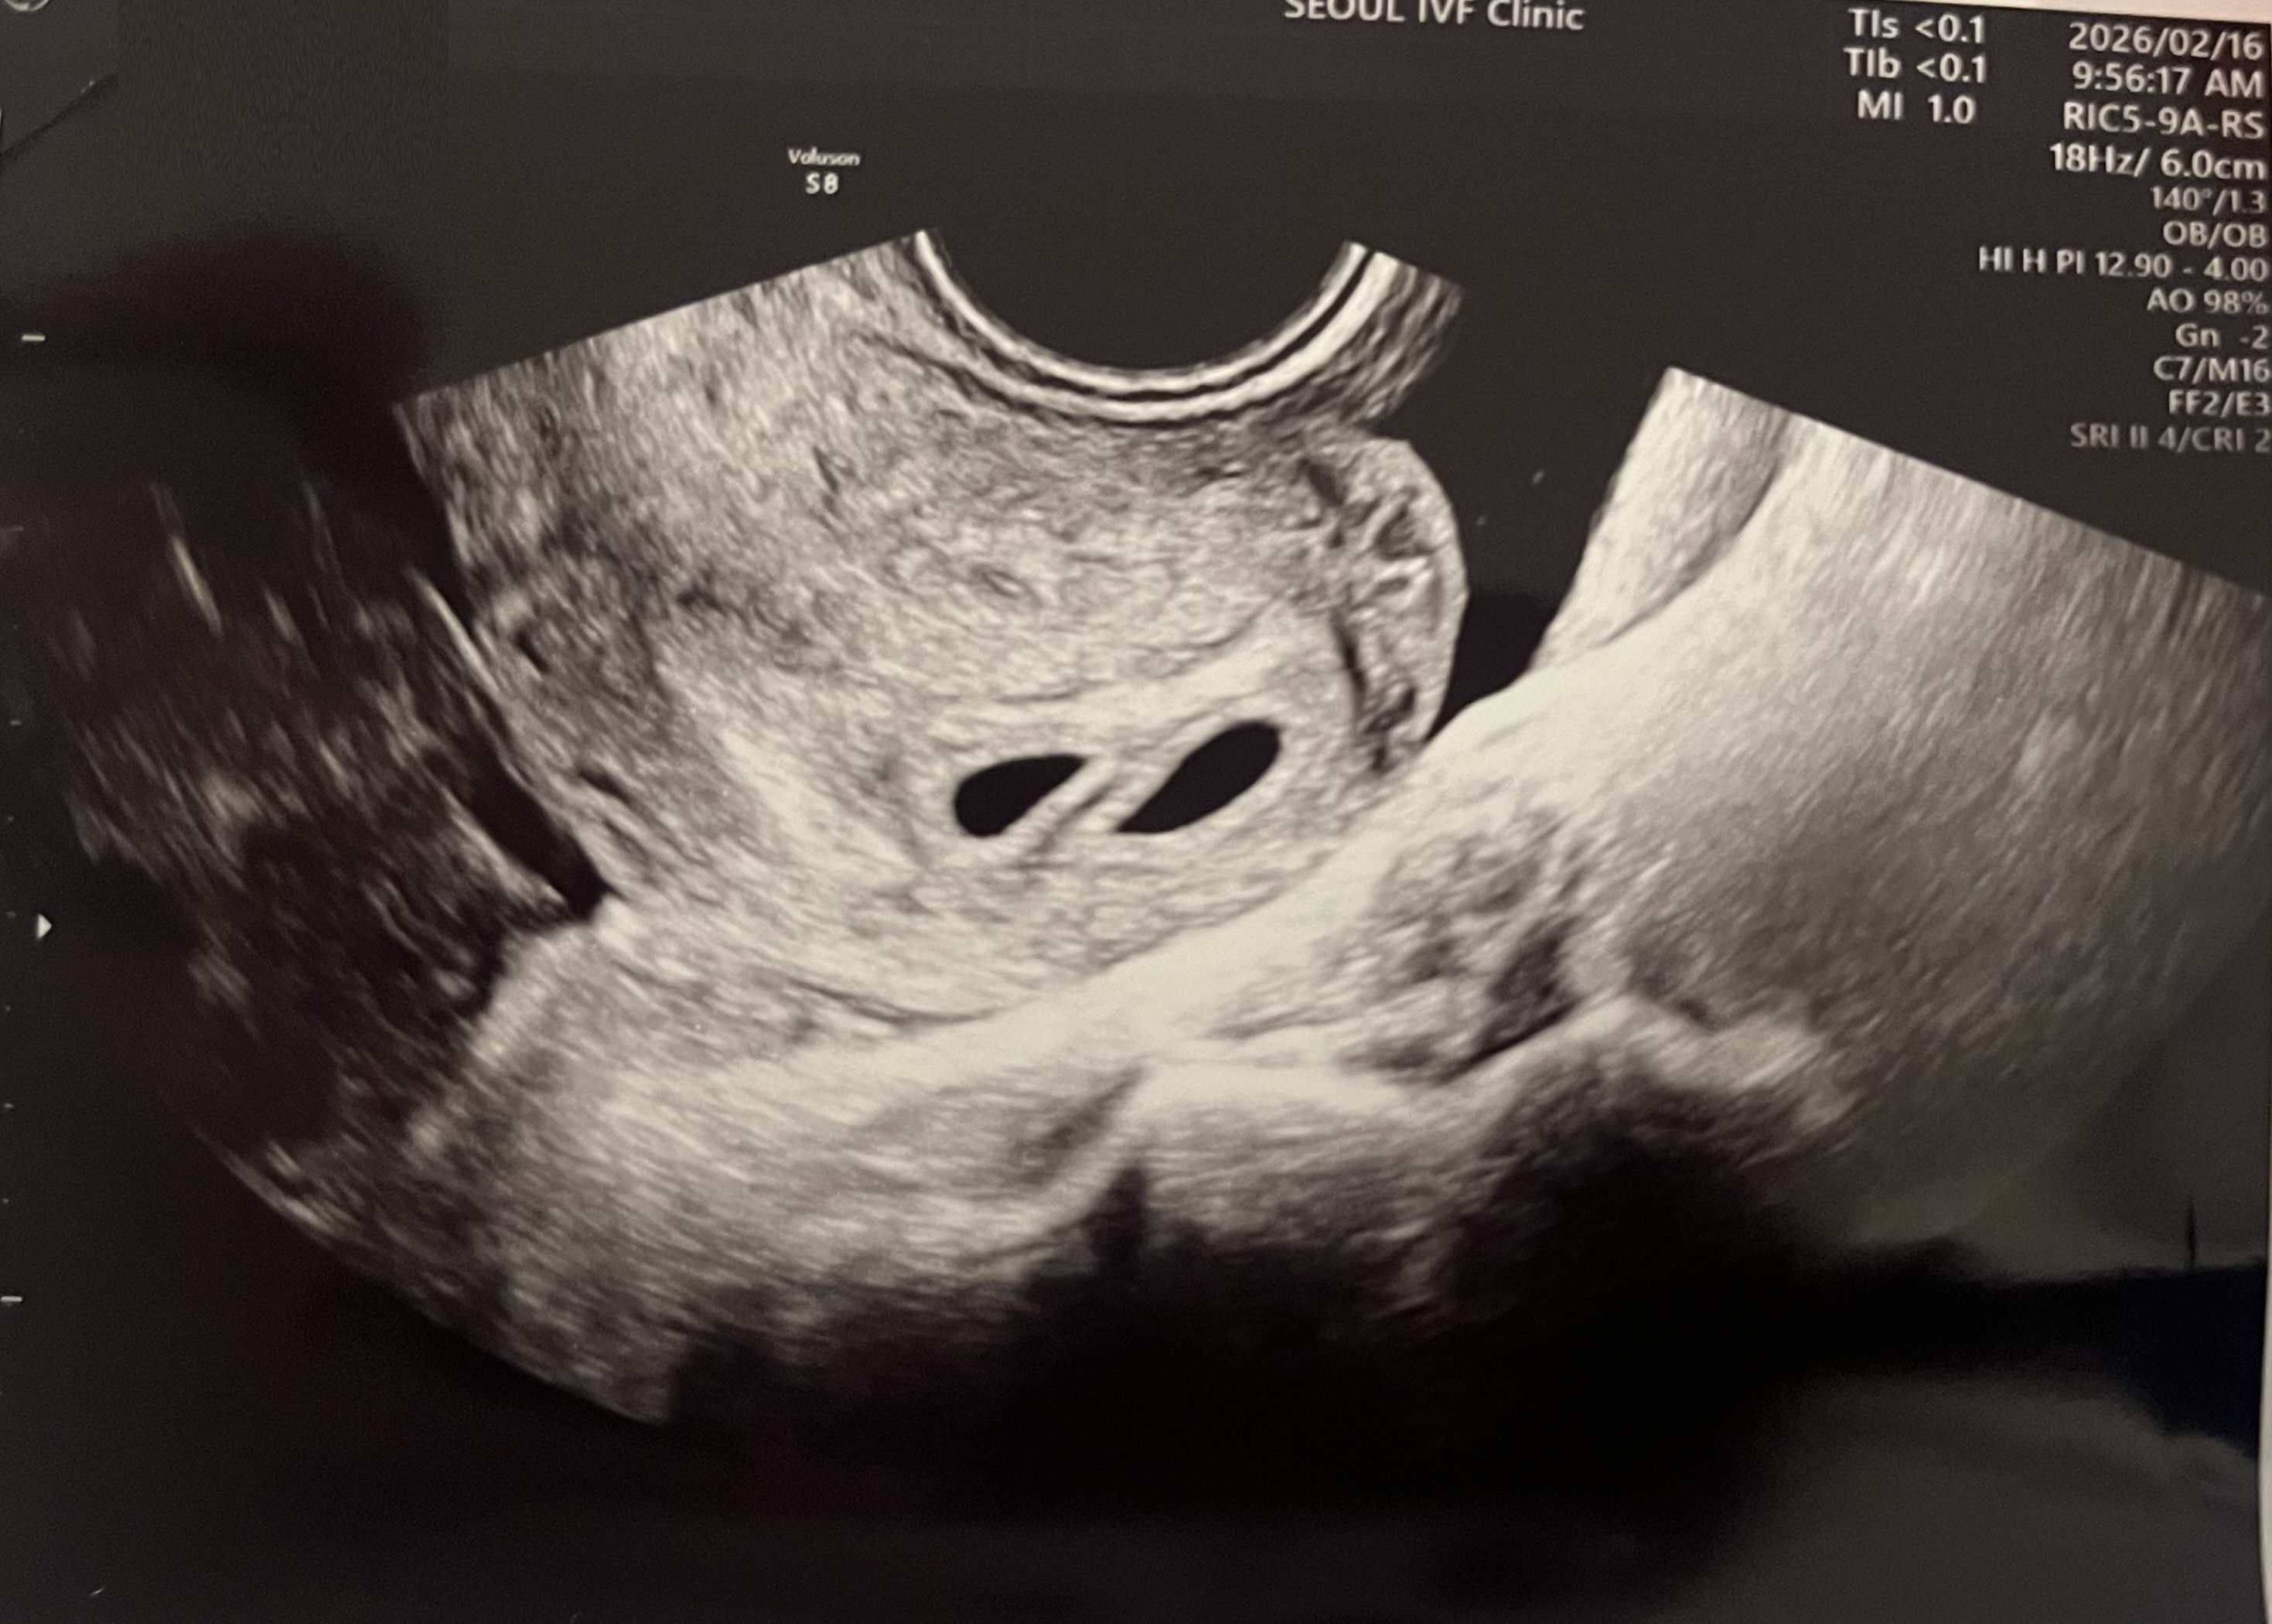

| 가슴 떨리는 임신 이야기를 공유해 주세요. | 한 번에 될 줄은 몰랐는데, 시험관 시도 후 빠르게 임신이 되어 놀랍고 감사한 마음이 큽니다. |

| 치료 도중 느꼈던 가장 기뻤던 순간과 절망적인 것들은 무엇인가요? 잊지 못할 경험이 있나요? | 가장 기뻤던 순간은 우리 아이의 심장소리를 처음 들었을 때였습니다. 절망적인 순간은 따로 없었습니다. |